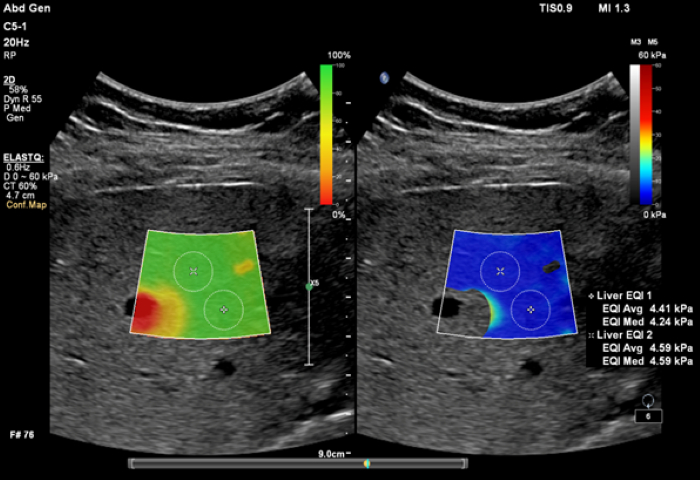

ElastQ Imaging produce una valutazione quantitativa in tempo reale a colori codificati della rigidità dei tessuti di vaste regioni di interesse (ROI). I medici possono valutare con facilità la rigidità del tessuto epatico con il feedback in tempo reale ed eseguire misurazioni quantitative con più punti di campionamento. ElastQ Imaging consente anche di eseguire misurazioni retrospettive sulle immagini archiviate. Un'esclusiva mappa di affidabilità utilizza un'analisi intelligente che aggiunge un ulteriore elemento di certezza alle misurazioni dell'utente, per appurare che siano state eseguite su aree di tessuto con una propagazione adeguata delle onde trasverse. Se utilizzata con la mappa della rigidità dei tessuti, la mappa di affidabilità dell'imaging aumenta l'attendibilità delle misurazioni dell'onda trasversa. Le due mappe possono essere visualizzate affiancate, e questo riduce il numero di fasi del flusso di lavoro e consente la correlazione simultanea delle mappe durante le fasi di acquisizione e misurazione.